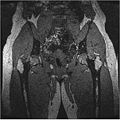

We have also proved that our algorithm works fairly well for hip dataset. Below are the MR images of Hip dataset we used.

The segmented output we got using our approach is